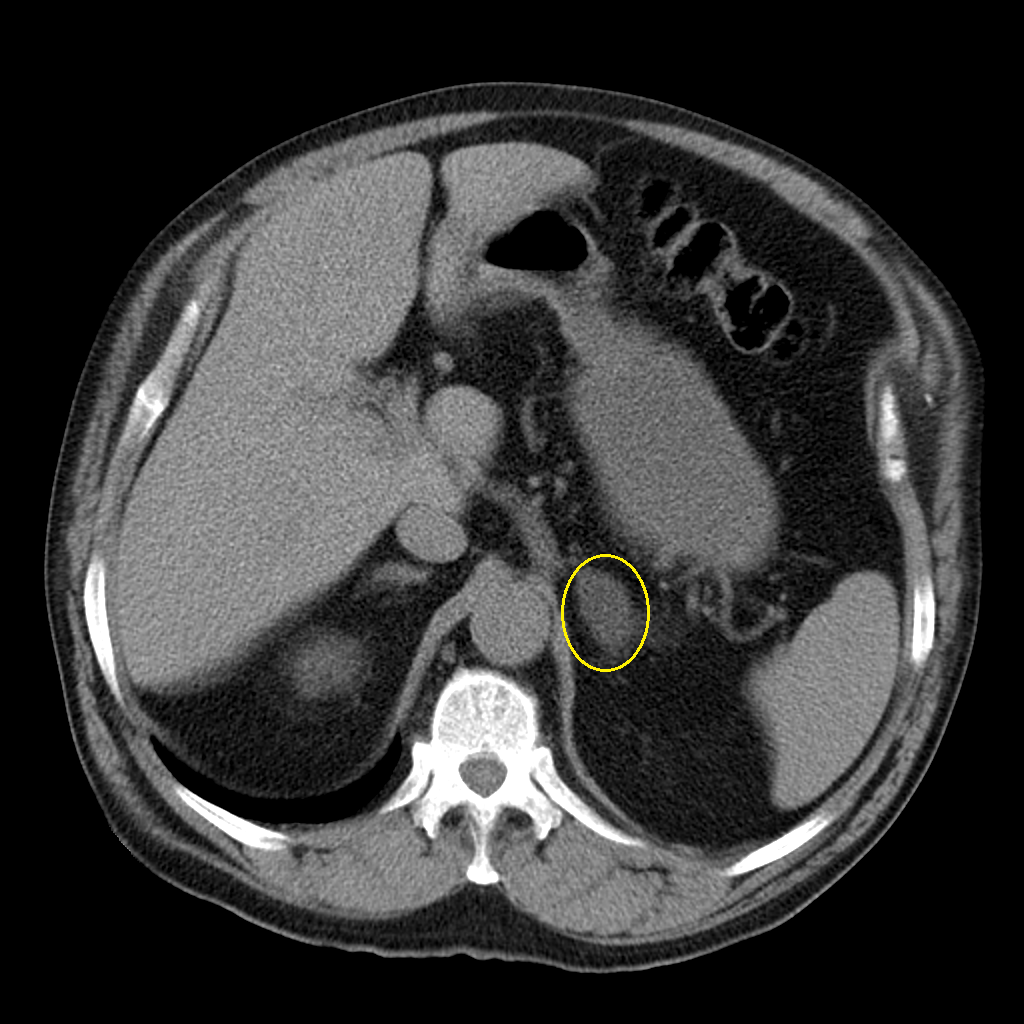

Ультразвуковые изображения анатомии надпочечников